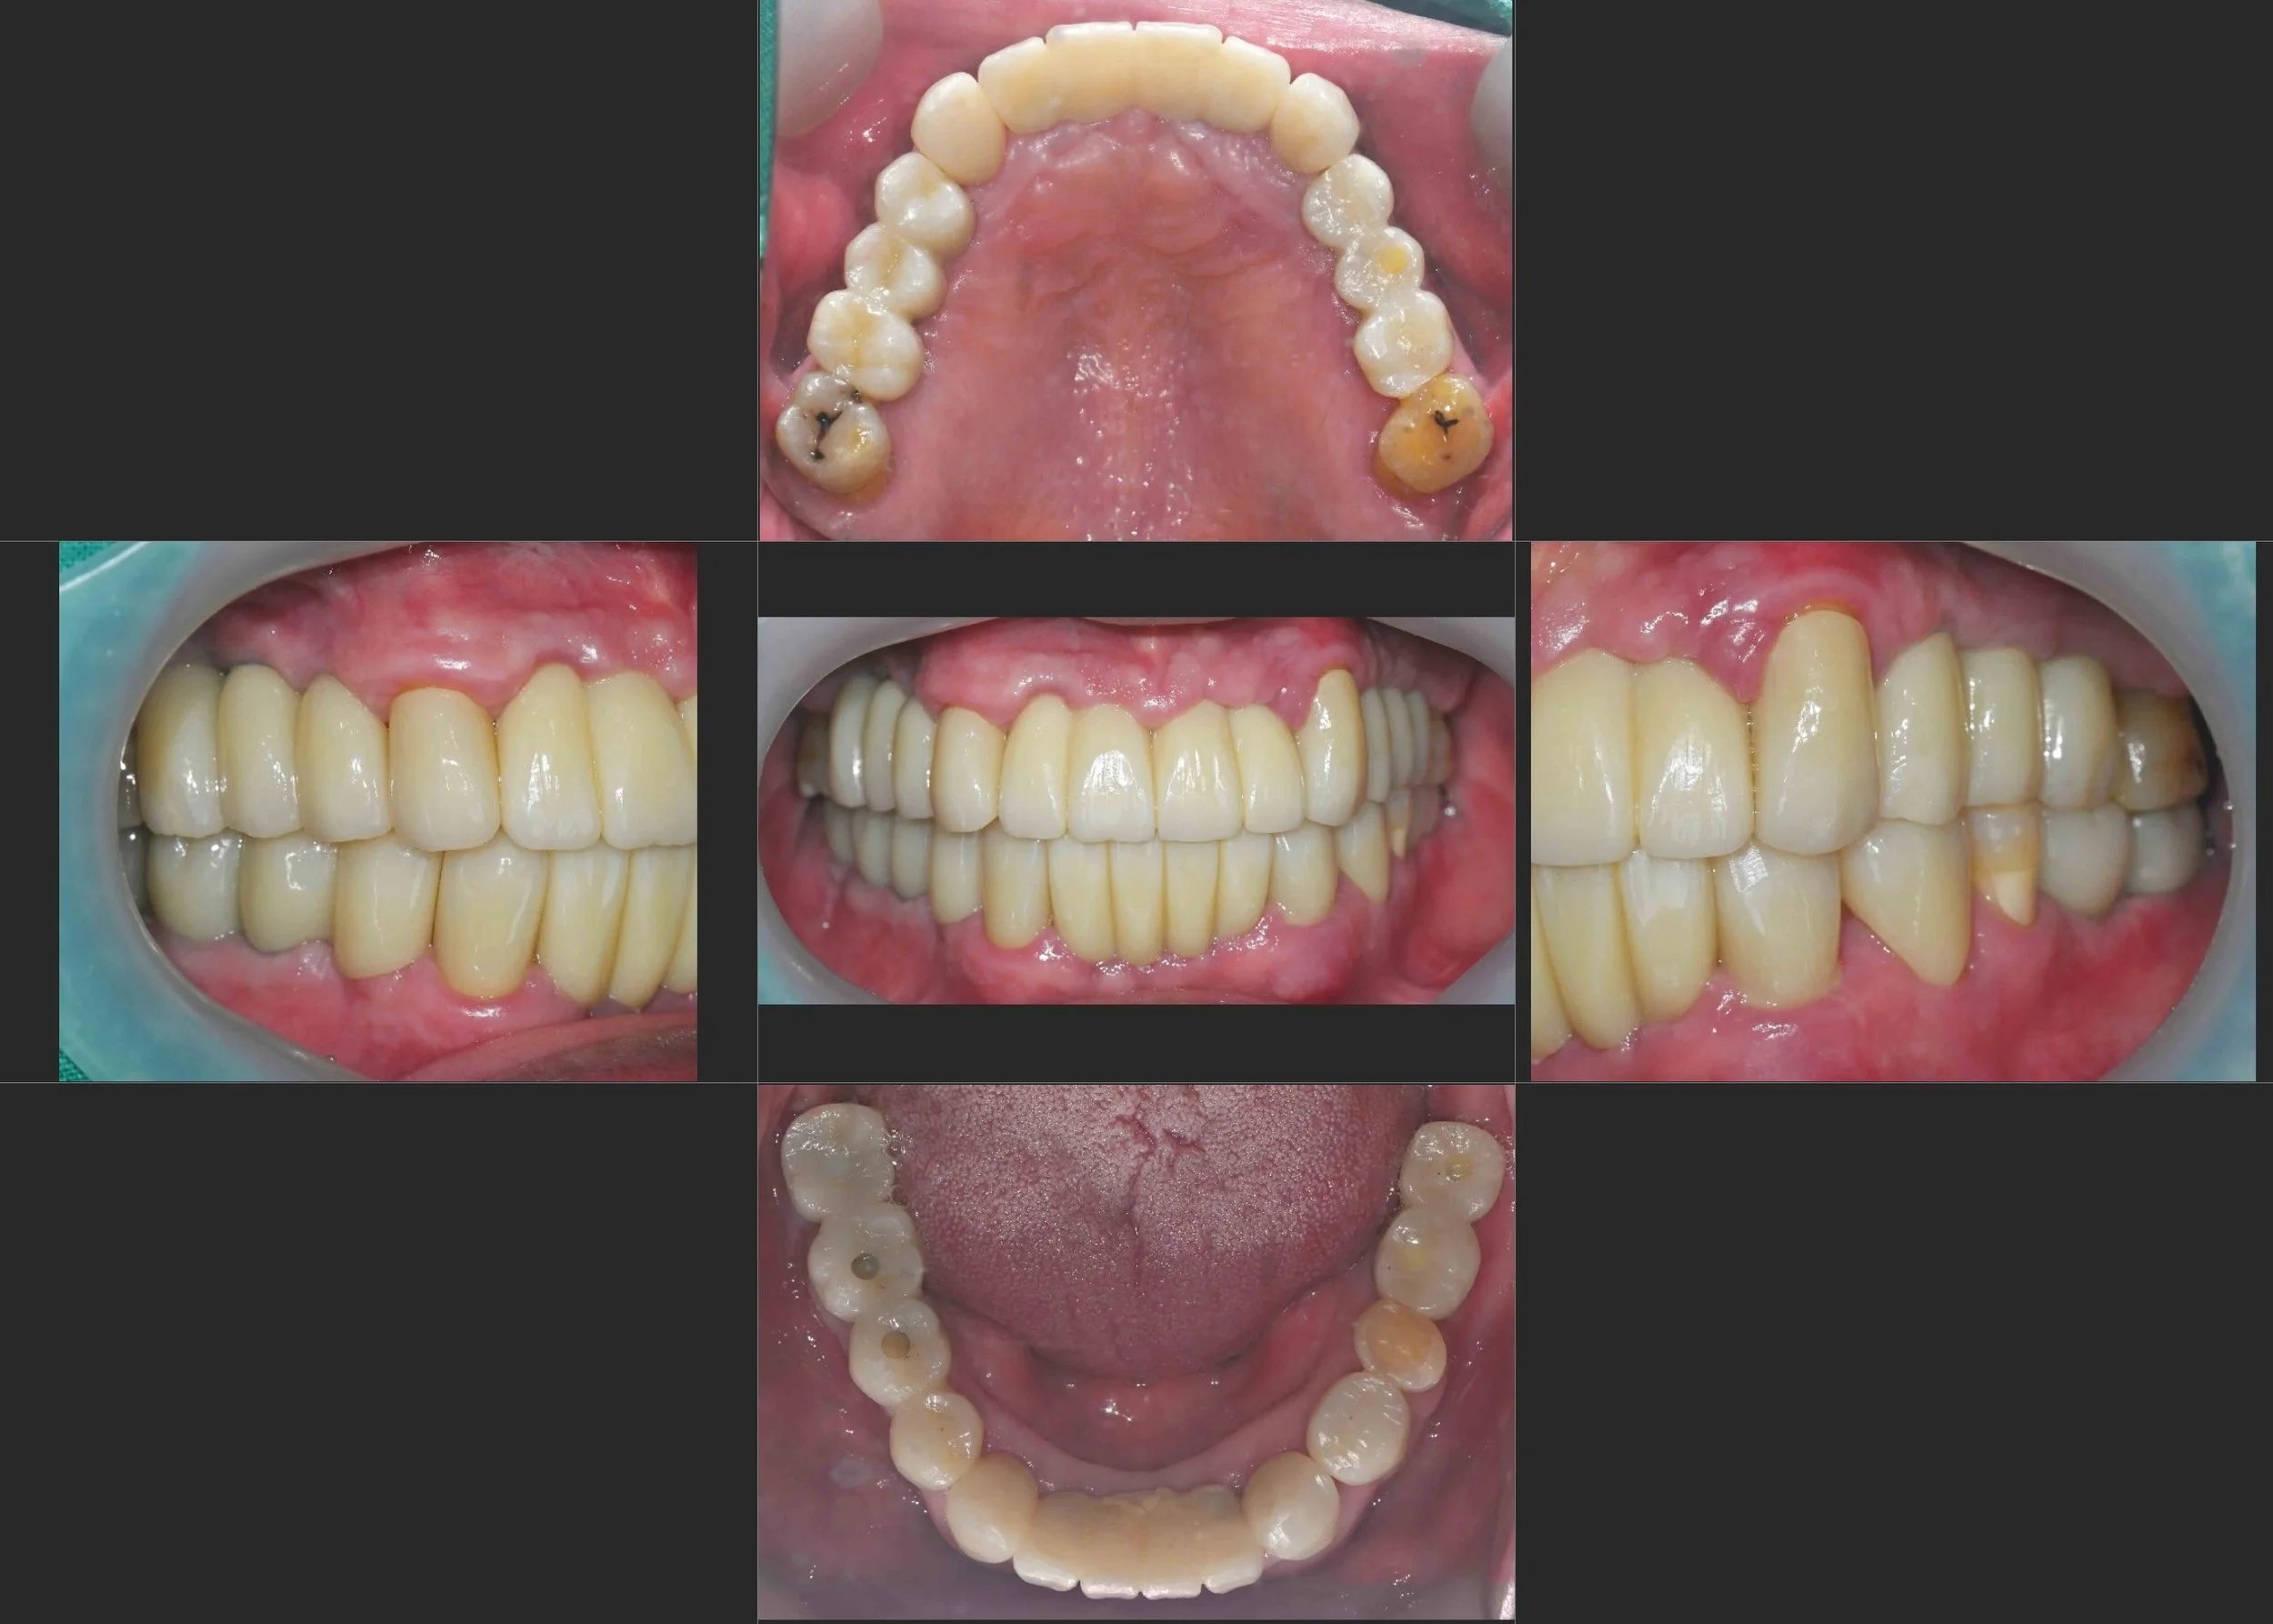

INTRA ORAL - AFTER

3. Prosthetic Reconstruction: Rather than a unified full-arch prosthesis, a combination of implant-supported bridges and tooth-supported crowns was utilized. This hybrid approach allowed for the preservation of the patient's biological proprioception (natural tooth feel).

4. Functional Calibration: The final occlusal relationship was meticulously calibrated to ensure even force distribution, protecting both the implants and the preserved natural teeth from excessive occlusal trauma.

The final result is a stable, functional, and aesthetic reconstruction that honors the patient's biological integrity while providing the structural support of modern implantology.